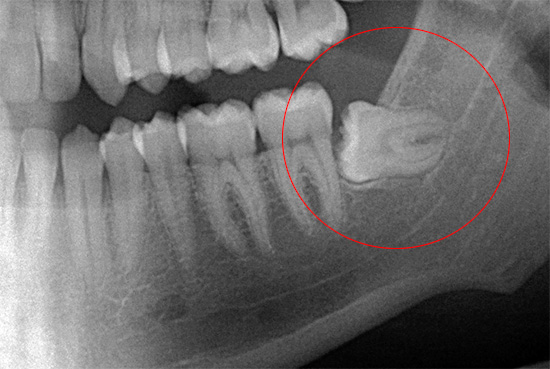

Devido à massa e densidade do osso da mandíbula, não é possível realizar uma aderência e balanço normais do dente (especialmente em caso de dificuldade em erupção, quando apenas 20 a 30% da coroa pode estar na superfície). Mesmo com uma coroa bem definida e sem cárie, o balanço do dente do siso inferior, localizado na espessura de um osso maciço, é muito, muito problemático, especialmente quando as raízes têm o número e a localização mais imprevisíveis na mandíbula.

De fato, as dobras e as rotações das raízes podem ser as mais incríveis. Freqüentemente, o dentista tem que lidar com duas ou mais raízes dobradas em ângulos diferentes, o que dificulta a extração de um dente que foi desapertado pelo cirurgião.

Por isso, antes de executar o procedimento de remoção, pode ser necessário fazer um raio-x de diagnóstico, permitindo que o dentista-cirurgião entenda com o que ele terá que lidar. Isso ajuda a evitar erros por parte do médico e também reduz o risco de possíveis complicações pós-operatórias.